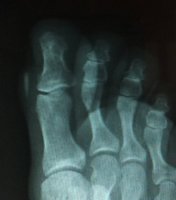

Fast forward to last month. I backpacked 12 miles and it started hurting like crazy. Whatever was in there was right under the skin and I could actually move it around a bit. So I go to my doc and he x-rays it. The radiologist report just said "12mm foreign object with the same density as bone". My report was "That looks like a catfish barb!".

But this would be lame without photos. For those that don't want to see photos of my x-rayed foot as well as a freshly removed chunk of catfish barb from my toe (a little blood), then don't click below to see the photos. Everyone else, proceed.

xray-zoom.jpg

It took the doc like 20 minutes of digging to get it out. The teeth of the barb kept it securely in place. That thing is just under a half an inch long.